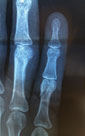

If you’ve injured or are experiencing pain in the fingertip with a fracture, swelling and bruising, you’ve come to the right place.

You may experience: Pain in the fingertip, Inability to bend the finger normally, often, you may have felt a ‘snap’ at the time the injury, The tip of your finger maybe sore to touch and swelling and bruising may develop later in the fingertip.

Choosing the right Hand Therapist starts with them being able to assess your injury, read your X-rays or Ultrasound and then educate and/or fabricate the right brace for you and your injury. The Hand Therapists, Physiotherapists and Occupational Therapists at Action Rehab Hand Therapy Clinic are experienced in assessing Jersey Finger and other tendon injuries, reading X-rays, reading Ultrasounds and advising on the most appropriate treatment.

Yes, always. Jersey Finger requires surgery. Hand Therapists at Action Rehab Hand Therapy Clinic can assess the finger, read the X-ray and can advise if your Jersey Finger injury needs surgery.